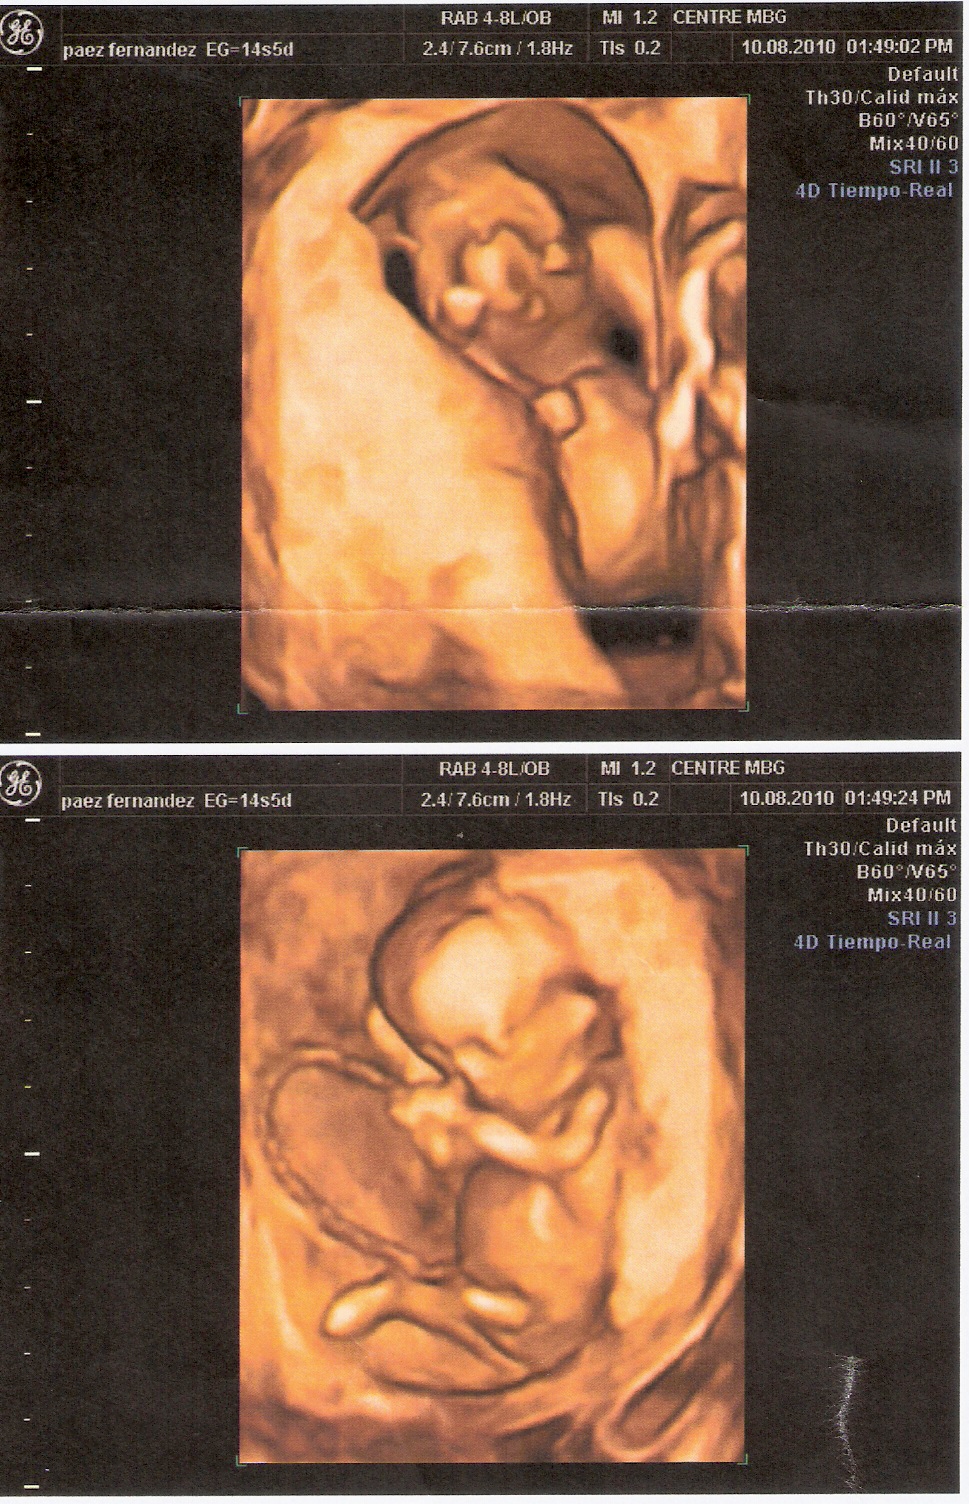

IN BTWIN Las ecografias de mis hermanos/ My brothers ultrasounds Do Twins Show Up On First Ultrasound healthcare providers can detect twins early using ultrasound. the international society of ultrasound in obstetrics and gynecology (isuog) recommends that twin fetuses. twins can show up on an ultrasound as early as 5 weeks into the pregnancy, but it’s also possible for an ultrasound to miss them. A twin pregnancy raises the risk of complications for the. Do Twins Show Up On First Ultrasound.

IN BTWIN Las ecografias de mis hermanos/ My brothers ultrasounds Do Twins Show Up On First Ultrasound This type of ultrasound allows. the international society of ultrasound in obstetrics and gynecology (isuog) recommends that twin fetuses. During this time, the ultrasound technician will look for two gestational sacs in the uterus, which can indicate twins. when can twins be seen on ultrasound? when it comes down to detecting twins in an ultrasound, it depends. Do Twins Show Up On First Ultrasound.